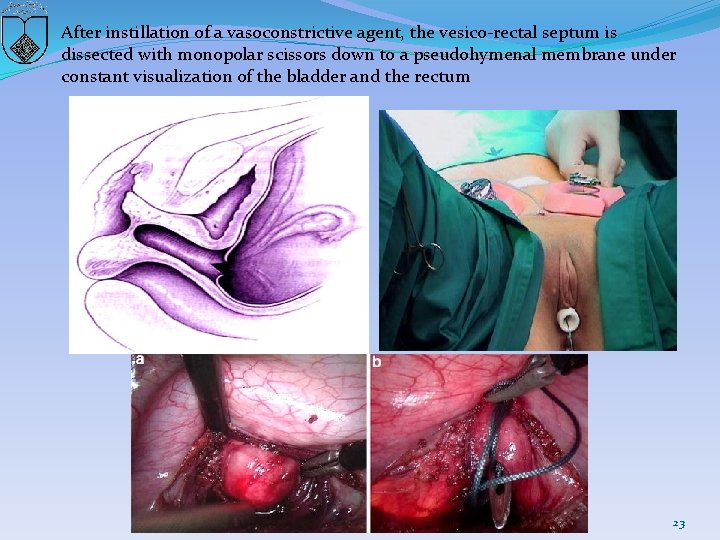

After instillation of a vasoconstrictive agent, the vesico-rectal septum is dissected with monopolar scissors down to a pseudohymenal membrane under constant visualization of the bladder and the rectum 23